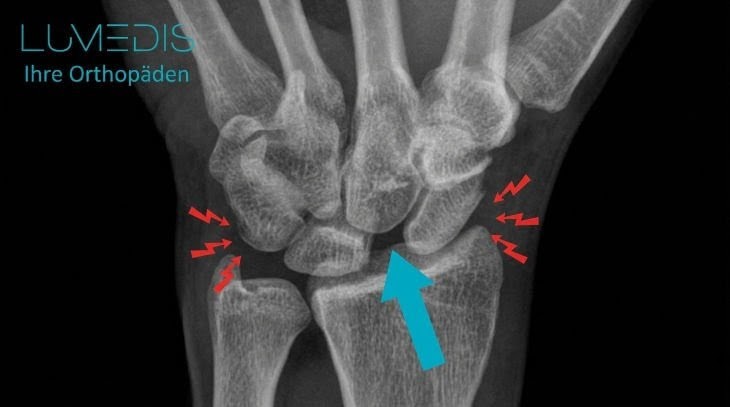

Röntgenbild einer scapholunäre Dissoziation (SLD)

Der türkise Pfeil zeigt auf die zu weit auseinander stehenden Handwurzelknochen von Kahnbein und Mondbein.

Bei einem echten Bänderriss kann zwischen den Knochen ein klaffender Gelenkspalt abgebildet sein, das größer als 2 mm ist.

In diesem Fall spricht man dann von einer Dissoziation dritten Grades.

Außerdem können neben dem Knochenabstand auch Begleitverletzungen wie Brüche anderer Knochen dargestellt und befunden werden.

Die häufigste mit der scapholunären Dissoziation verbundene Verletzung ist die Fraktur des Kahnbeins.

Hier können neben „großen“ Frakturen auch Mikrofrakturen im Röntgen auftauchen. Bänder und Sehnen sind hingegen im Röntgen hier nicht gut sichtbar.